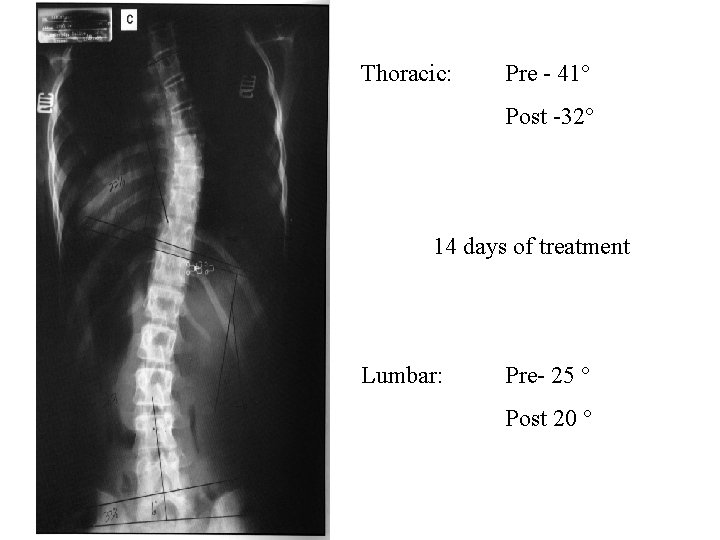

Thoracic: Pre - 41° Post -32° 14 days of treatment Lumbar: Pre- 25 ° Post 20 °